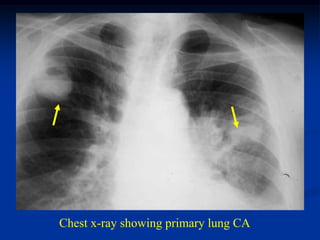

Chest x-ray showing primary lung CA

Case #1143.1

55 year male with

subtroch path fracture

2nd to metastatic lung CA